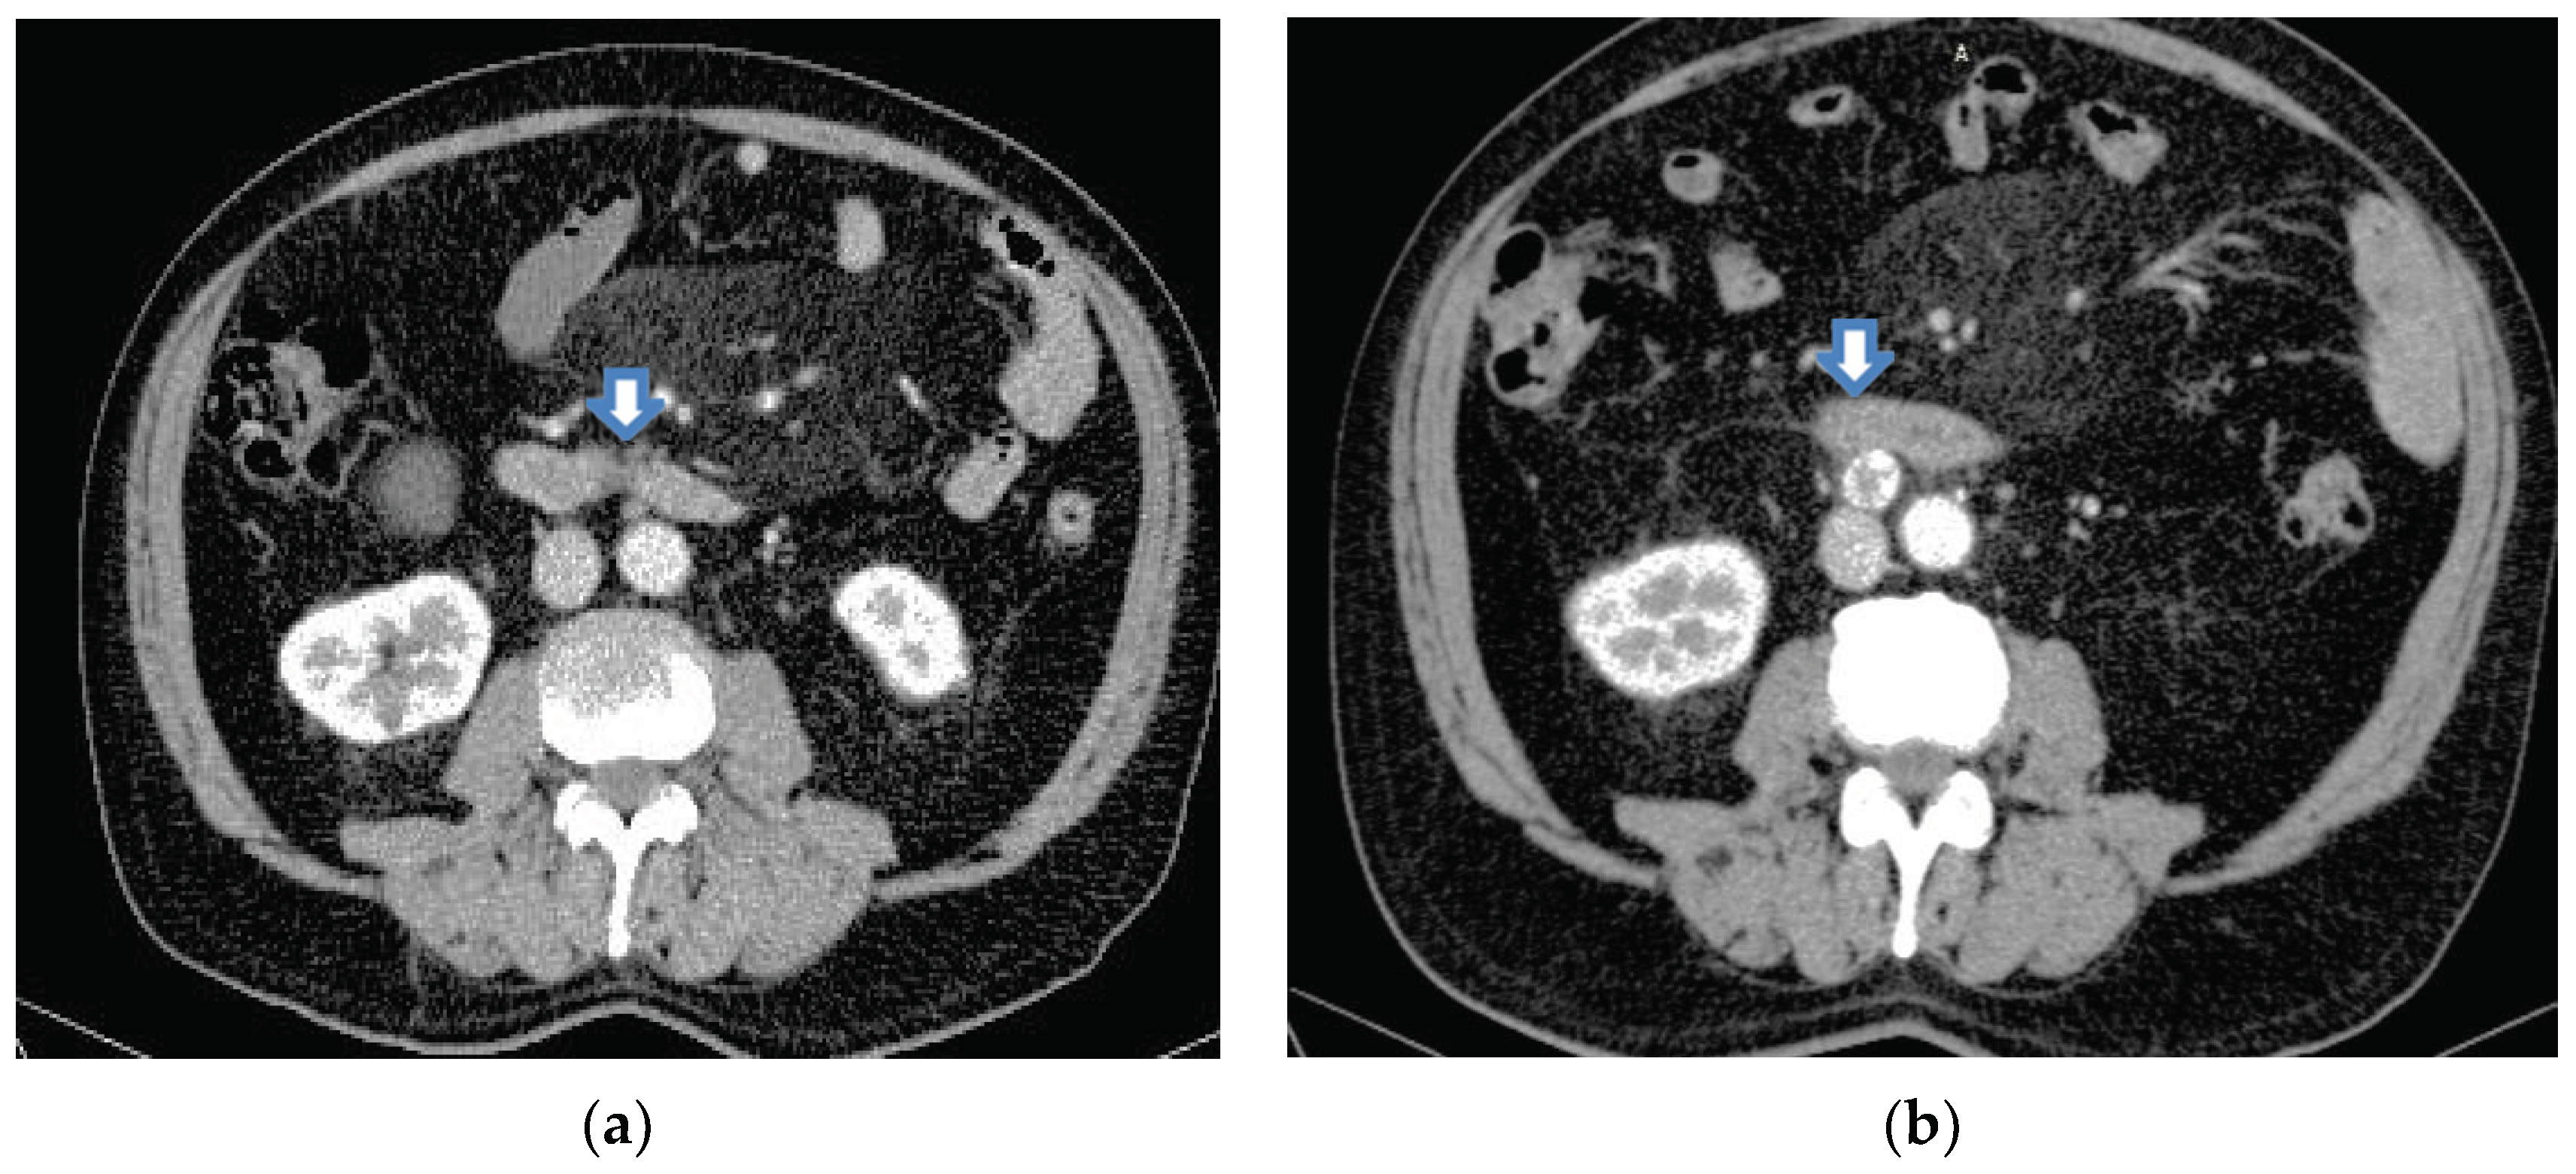

2.3. Imaging Tests